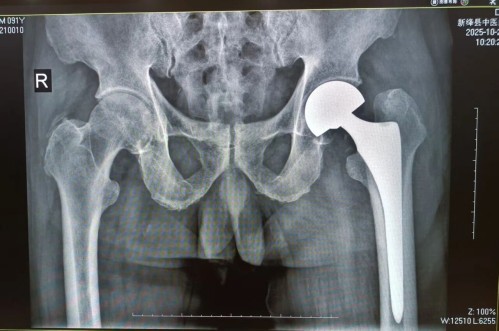

为确保手术万无一失,医护团队术前对贾大爷的心肺功能、血压、血糖等各项指标进行全面评估,联合麻醉科制定个性化麻醉方案,同时对患者及家属进行心理疏导,讲解手术流程和术后康复要点,缓解其焦虑情绪。手术当天,郝晓斌副院长带领团队精准操作,凭借精湛的医术的和默契的配合,历时1小时顺利完成人工股骨头置换手术,术中出血少、创伤小,达到了预期效果。

术后X片